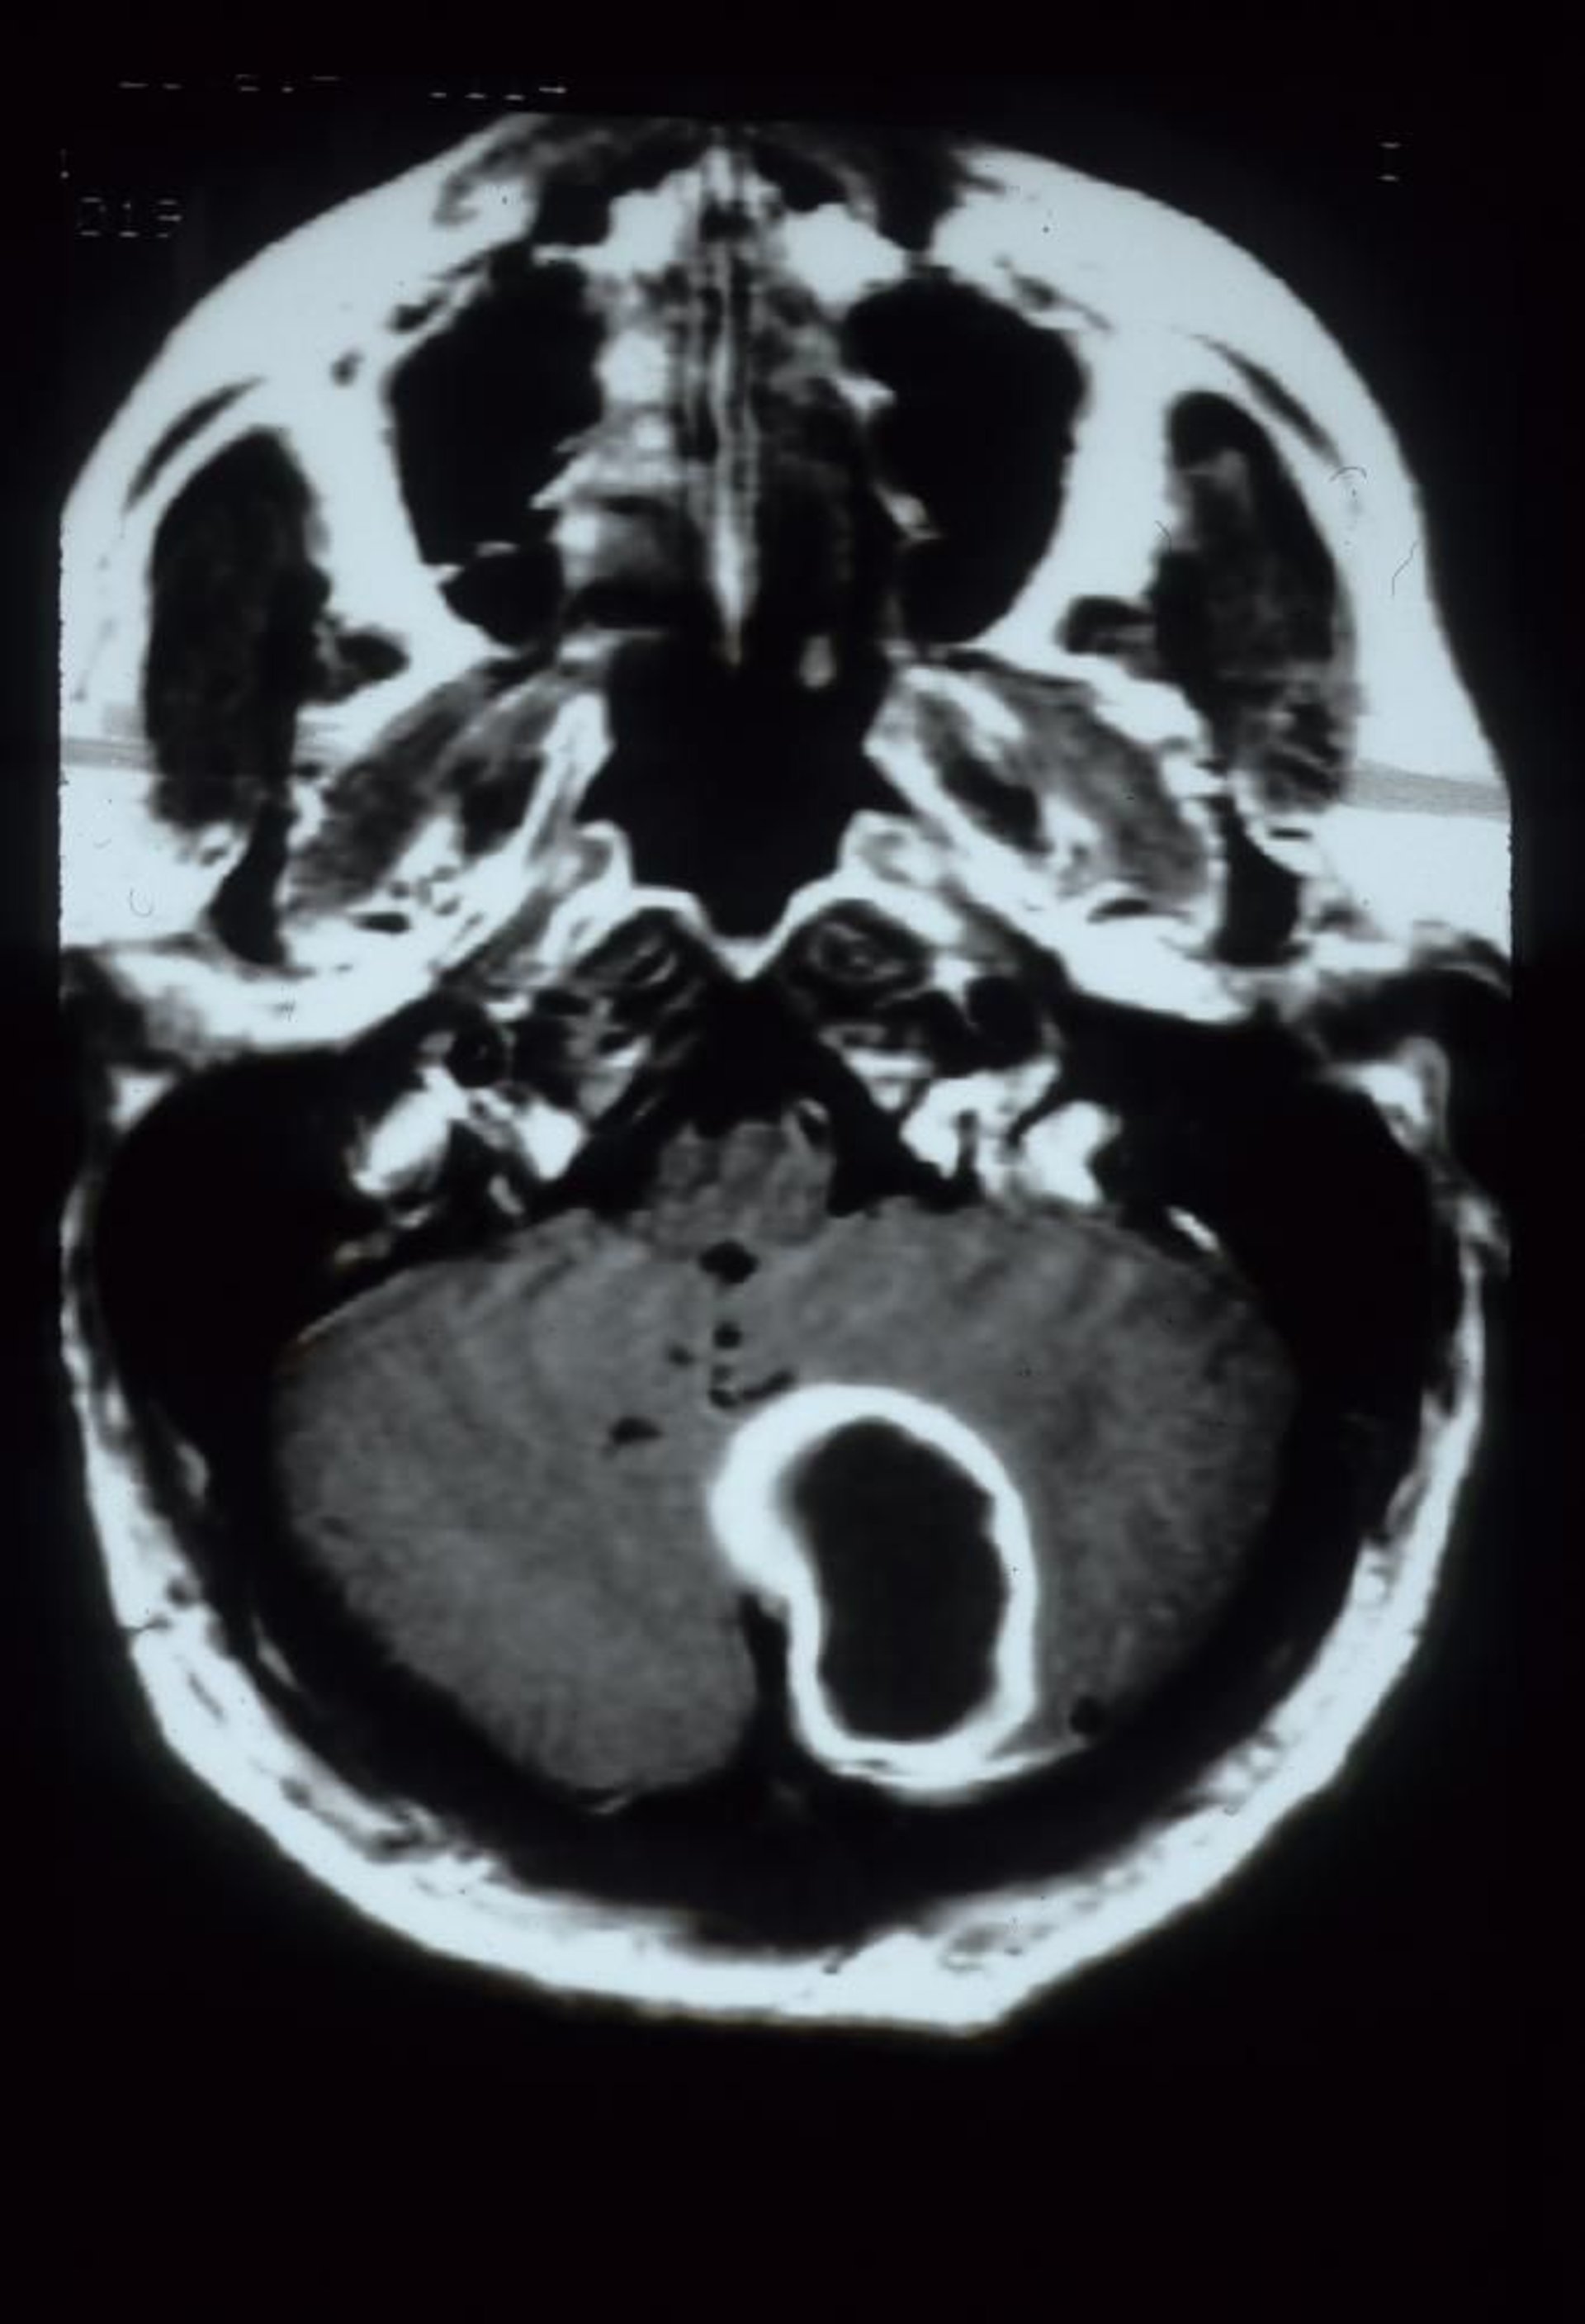

Kleinhirnabszess

Diese gadoliniumverstärkte MRT-Aufnahme zeigt einen Kleinhirnabszess, der als große, randverstärkte kavitäre Läsion in der linken Kleinhirnhemisphäre erscheint.

Courtesy of John E. Greenlee, MD.